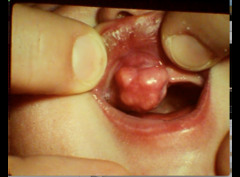

mucocele

-localized tissue swelling that increases and decreases in size most commonly on lower lip -severed salivary gland duct -mucous filled

chronic hyperplastic pulpitis

-Red or pink nodule protruding from the pulp chamber or a tooth with a large open carious lesion (usually molars)